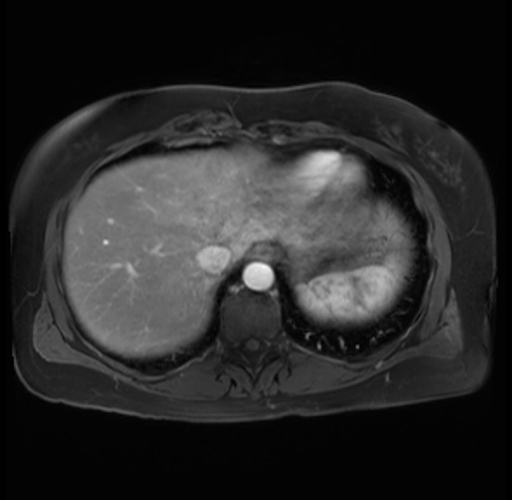

Imaging Analysis

Look through the patient's CT scan to identify any areas of concern for the necessary procedure.

Based on your CT findings, which issue(s) are present and would give reason for "planned slowing down moment(s)" in this case?

Considering a standard distal pancreatectomy procedure, what step(s) of the operation would you do differently in this case?